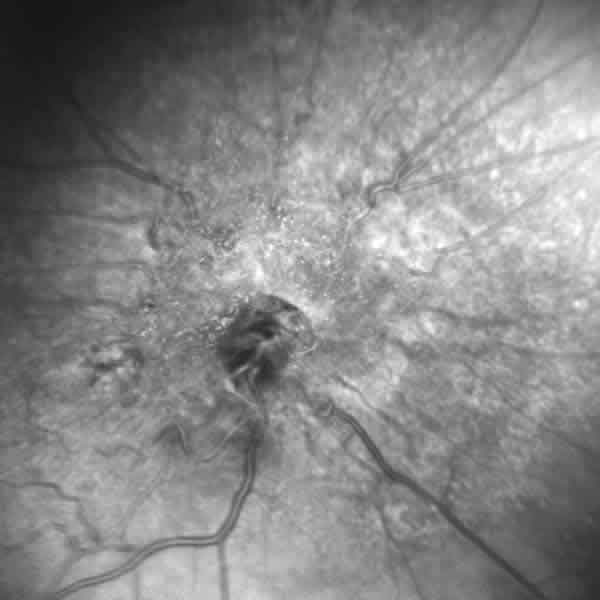

Varón de 65 años con historia de pérdida progresiva de agudeza visual en su OD. La MAVC fue 0,1 en OD y 1,0 en OI. En la funduscopía del OD (fig. 4) se detectó una elevación del nervio óptico con pigmentación dispersa, acompañada de tortuosidad de los vasos peripapilares, con membrana epirretiniana y edema macular quístico. La AFG (fig. 5) demostró hipofluorescencia precoz con hiperfluorescencia tardía a partir de fuga desde los vasos dilatados y tortuosos, sin evidencia de neovascularización coroidea. La OCT (fig. 6) ilustra lesión hiperreflectiva temporal a la papila con desestructuración retiniana y engrosamiento macular quístico de 394 µm, además de una llamativa membrana epirretiniana.

Fig. 4: Caso 2. Masa elevada en el nervio óptico con dispersión pigmentaria y telangiectasias.